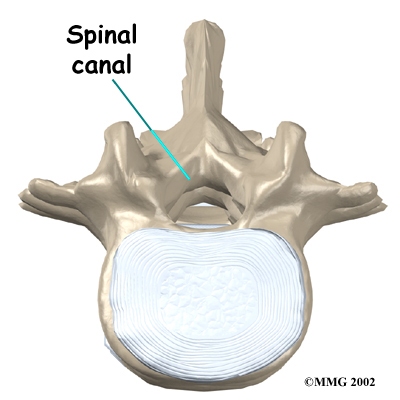

Each vertebra is formed by a round block of bone, called a vertebral body. A attaches to the back of the vertebral body. When the vertebrae are stacked on top of each other, these bony rings create a hollow tube. This tube, called the spinal canal, surrounds the as it passes through the spine. Just as the skull protects the brain, the bones of the spinal column protect the spinal cord.

The spinal cord only extends to L2. Below this level, the spinal canal encloses a bundle of nerves that goes to the lower limbs and pelvic organs. The Latin term for this bundle of nerves is , meaning horse's tail.

Two sets of bones form the spinal canal's . Two pedicle bones attach to the back of each vertebral body. Two lamina bones complete the ring. The place where the lamina and pedicle bones meet is called the pars interarticularis, or pars for short. There are two such meeting points on the back of each vertebra, one on the left and one on the right. The pars is thought to be the weakest part of the bony ring.

Slippage can also cause nerve compression. Nerve compression is a result of . As the spine slips forward, the nerves may be squeezed where they exit the spine. This condition also reduces space in the spinal canal where the vertebra has slipped. This can put extra pressure on the nerve tissues inside the canal. Nerve compression can cause symptoms where the nerve travels and may include numbness, tingling, slowed reflexes, and muscle weakness in the legs.

Nerve pressure on the cauda equina (mentioned earlier), the bundle of nerve roots within the lumbar spinal canal, can affect the nerves that go to the bladder and rectum. When this happens, bowel and/or bladder function can be affected. The pressure may cause low back pain, pain running down the back of both legs, and numbness or tingling between the legs in the area you would contact if you were seated on a saddle.

When the vertebra slips forward, the nearby nerves that exit the spine can become pinched or irritated. In addition, the size of the spinal canal in the problem area shrinks, placing pressure on the nerves inside the canal. To fix this, the lamina of the bony ring is removed to ease pressure on the nerves. The procedure to remove the lamina and release pressure on the nerves is called . Decompression alone is usually not advised. Studies show much better results when the operation is combined with a fusion of the involved vertebrae (see below).